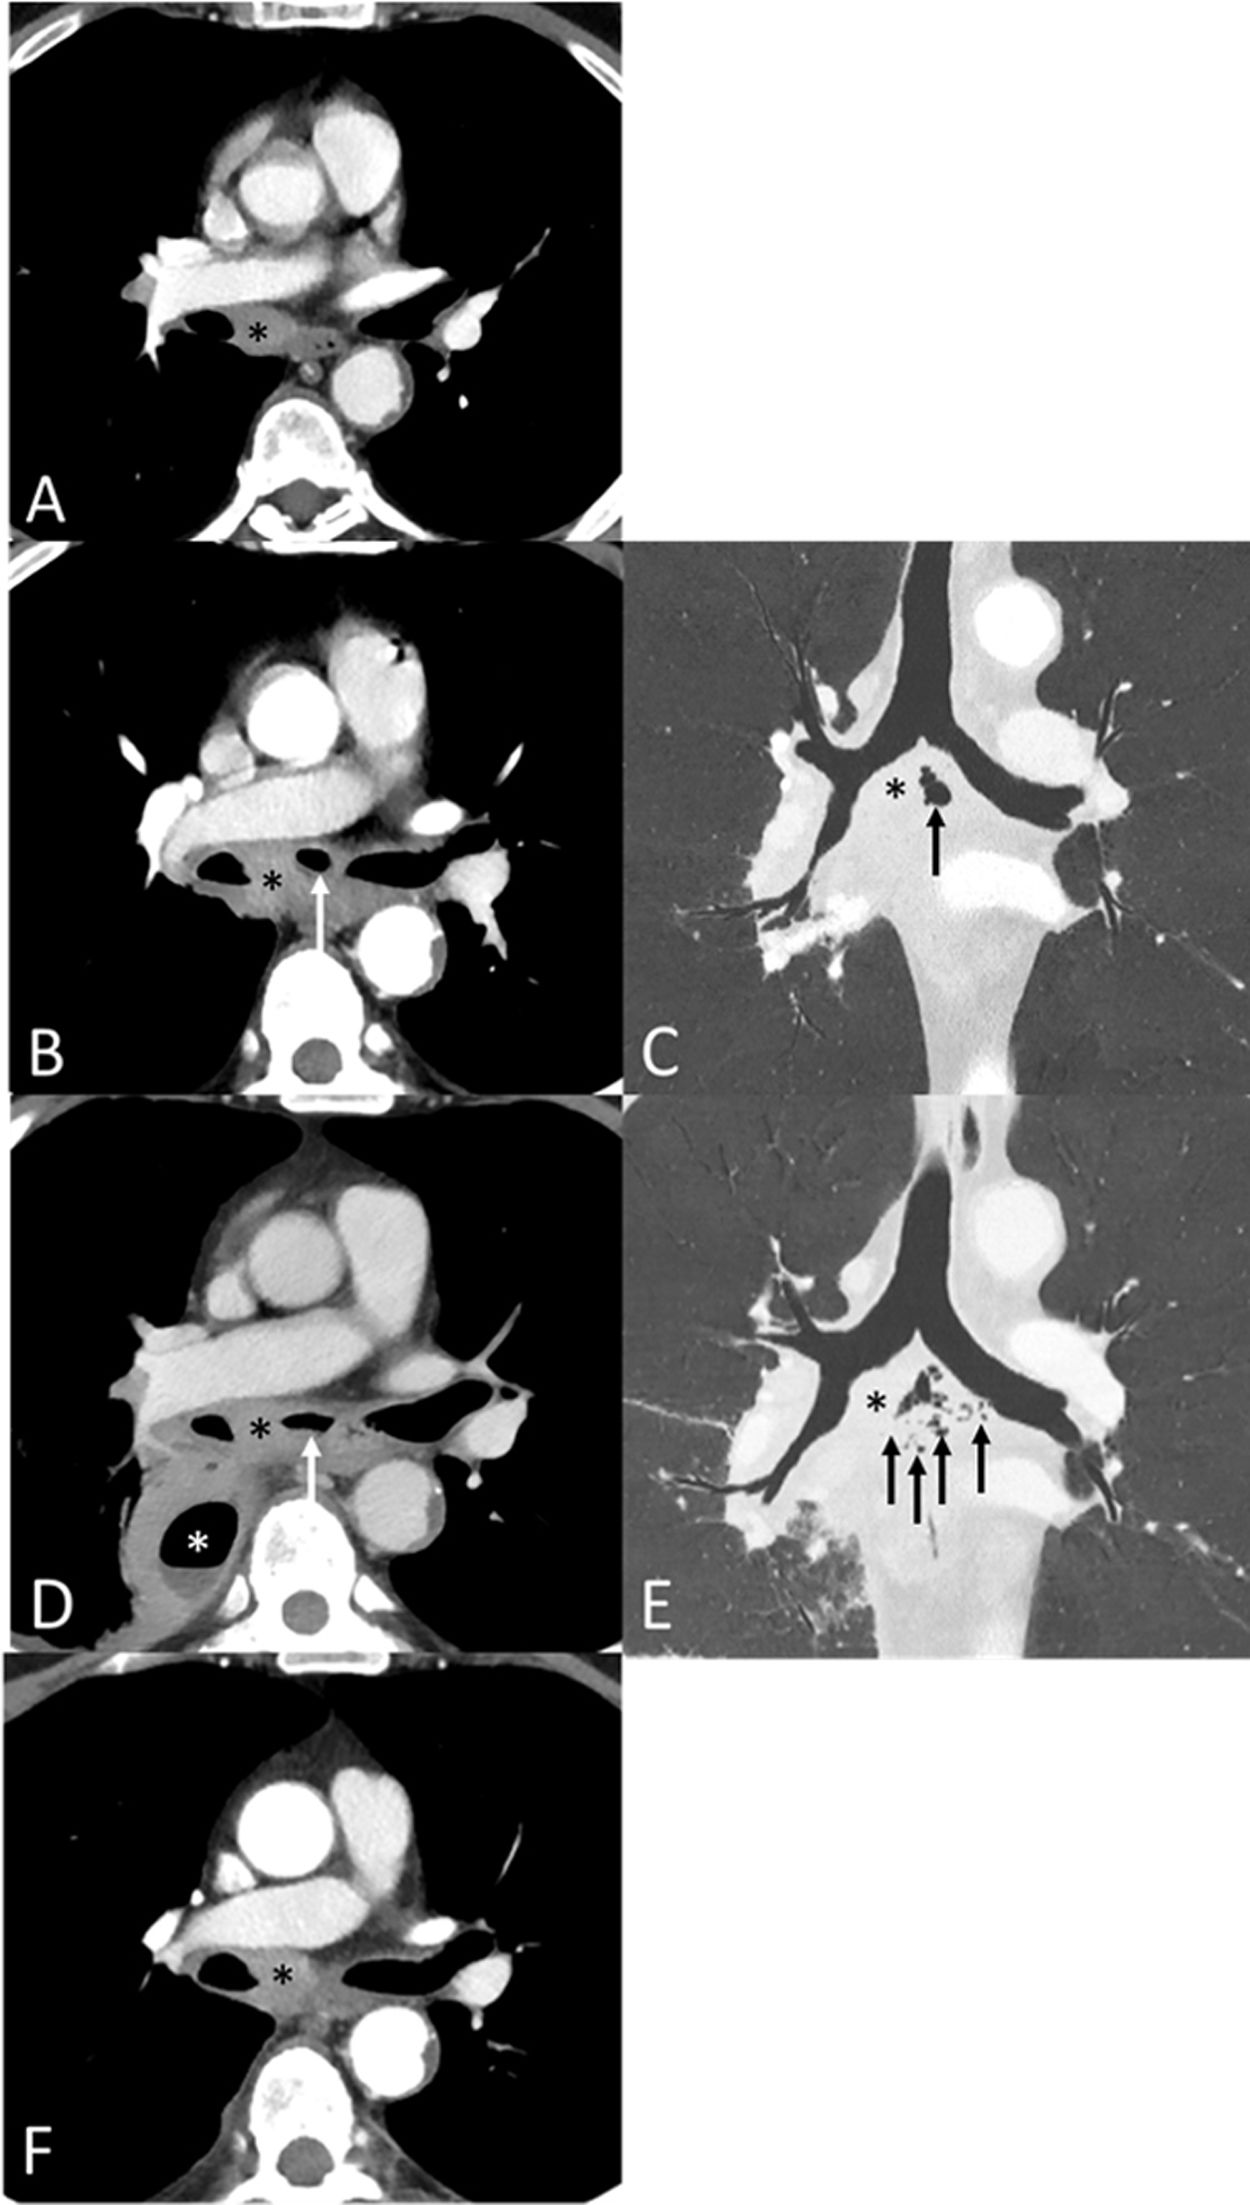

A follow-up CT in a 58-year-old stage III lung cancer patient (without any other relevant comorbidities) who had started systemic pembrolizumab in combination with chemotherapy 8 weeks earlier showed an enlargement of a dominant subcarinal lymph node with appearance of intranodal necrosis and air. The patient denied any fever, dyspnea or dysphagia. Four weeks later the patient developed fever, an elevation of acute phase reactants was observed, and a new CT showed more intranodal air extending outside the boundaries of the subcarinal lymph node and the appearance of a loculated pleural effusion adjacent to the necrotic partly-cavitary subcarinal lymphadenopathy. The decision was made to stop the chemo-immunotherapy and to start antibiotic treatment (piperacillin/tazobactam). A bronchoscopy did not show any bronchonodal fistula. A CT-guided percutaneous drainage of the pleural effusion was also performed and yielded purulent fluid (Streptococcus anginosus was isolated in the pleural fluid). A presumptive diagnosis of an emphysematous subcarinal lymphadenitis complicated with a pleural empyema was made. The patient responded well to the percutaneous drainage of the pleural cavity and to the administration of antibiotics (Fig. 1), and he resumed his cancer treatment 1 month after it was suspended. To our knowledge, spontaneous emphysematous mediastinal lymphadenitis complicated with a pleural empyema has not been previously described. We believe that early intervention combining systemic treatment with antibiotics and pleural drainage may be an effective approach to this rare complication.

(A) Axial image (mediastinal window) from the baseline CT study shows an enlarged homogeneous subcarinal lymph node normal. (B and C) Axial (B, mediastinal window) and coronal (C, lung window) images from a follow-up CT study performed 8 weeks after initiation of chemo-immunotherapy shows enlargement of the subcarinal lymph node (asterisk) and the appearance of intranodal air (arrow); note the lack of communication of the intranodal air with the airway. (D and E) Axial (D, mediastinal window) and coronal (E, lung window) images from a CT study performed 4 weeks after B and C demonstrate further enlargement of the subcarinal lymph node (black asterisk) and the appearance of a loculated right pleural effusion (white asterisk) with an air-fluid level (hydropneumothorax); note the presence of more air bubbles within and surrounding the subcarinal lymph node (arrows). (F) Axial (mediastinal window) CT image from a study performed 4 weeks after D and E shows a decrease in the size of the subcarinal lymph node (asterisk), and disappearance of the right pleural effusion and of both the intranodal and perinodal air.